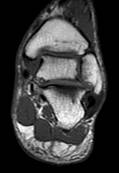

При МР-томографии интенсивность сигнала задней малоберцово-таранной связки повышена на Т2 ВИ, контуры прерывисты.

|

| Рис 2. Аксиальная и коронарная плоскости сканирования. Т2 ВИ. Стрелкой показан полный разрыв задней малоберцово-таранной связки. В коронарной плоскости (б) можно лишь предположить наличие повреждения, а на аксиальной (а) это полностью подтверждено. | ||||

| Рис 3. Саггитальная плоскость сканирования. Т2 и Т1 ВИ. Стрелками указаны повышенное скопление жидкости в переднем и заднем заворотах, в полости суставов – большеберцово-таранном и таранно-пяточном. Повреждение каких-либо связок можно лишь предположить. |